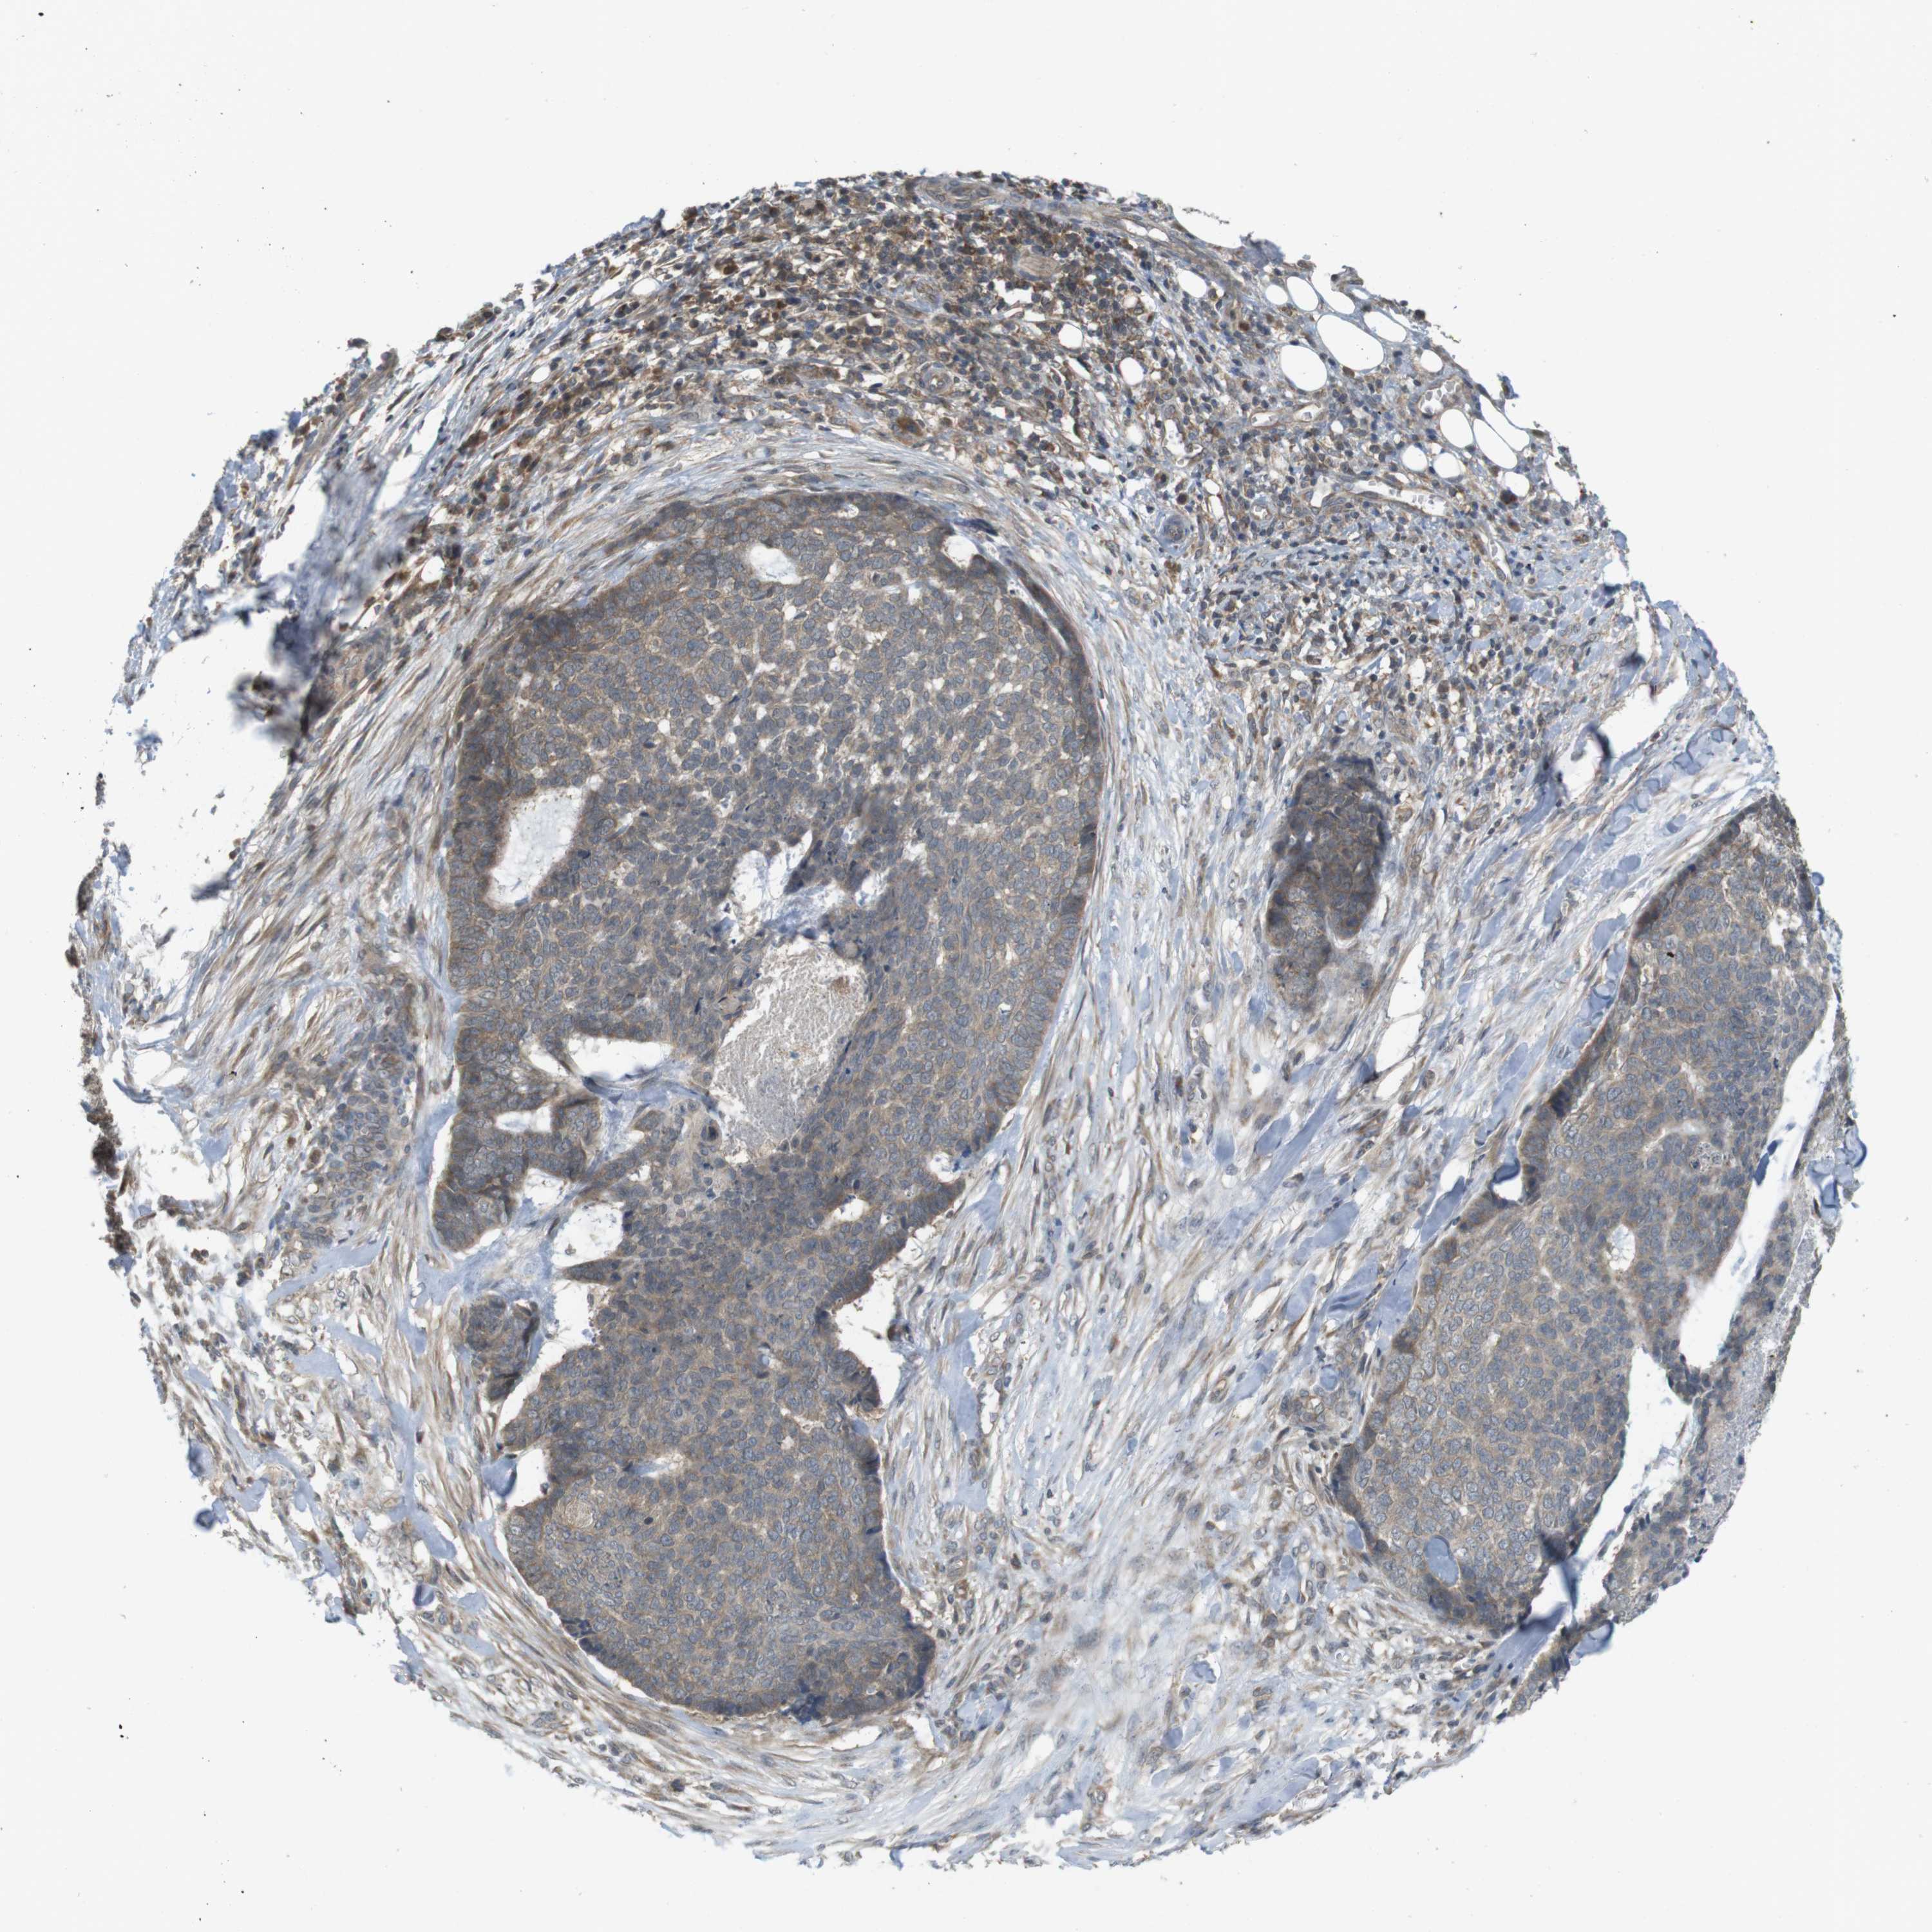

SKIN CANCER

Basal cell and squamous cell cancer